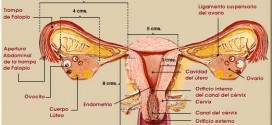

Leer MásNEOPLASIAS DEL APARATO GENITAL O EXTRAGENITAL FEMENINO

Las neoplasias del aparato genital o extragenital femenino. Ver cáncer de ovario. Si fuese de su deseo le podemos elaborar un plan trofológico personalizado para usted.

Leer MásTUMOR OVÁRICO MUCINOSO

Los tumores mucinosos están caracterizados por quistes y glándulas revestidas por células que contienen moco. Representan un 15% de los tumores ováricos. Aproximadamente un 75% son benignos, un 10% borderline; y un 15%, carcinomas. Los tumores de ovario mucinoso, representan el 15% de los tumores epiteliales de ovario, pudiendo corresponder a la estirpe serosa, mucinosa, endometrioide, células claras o células …